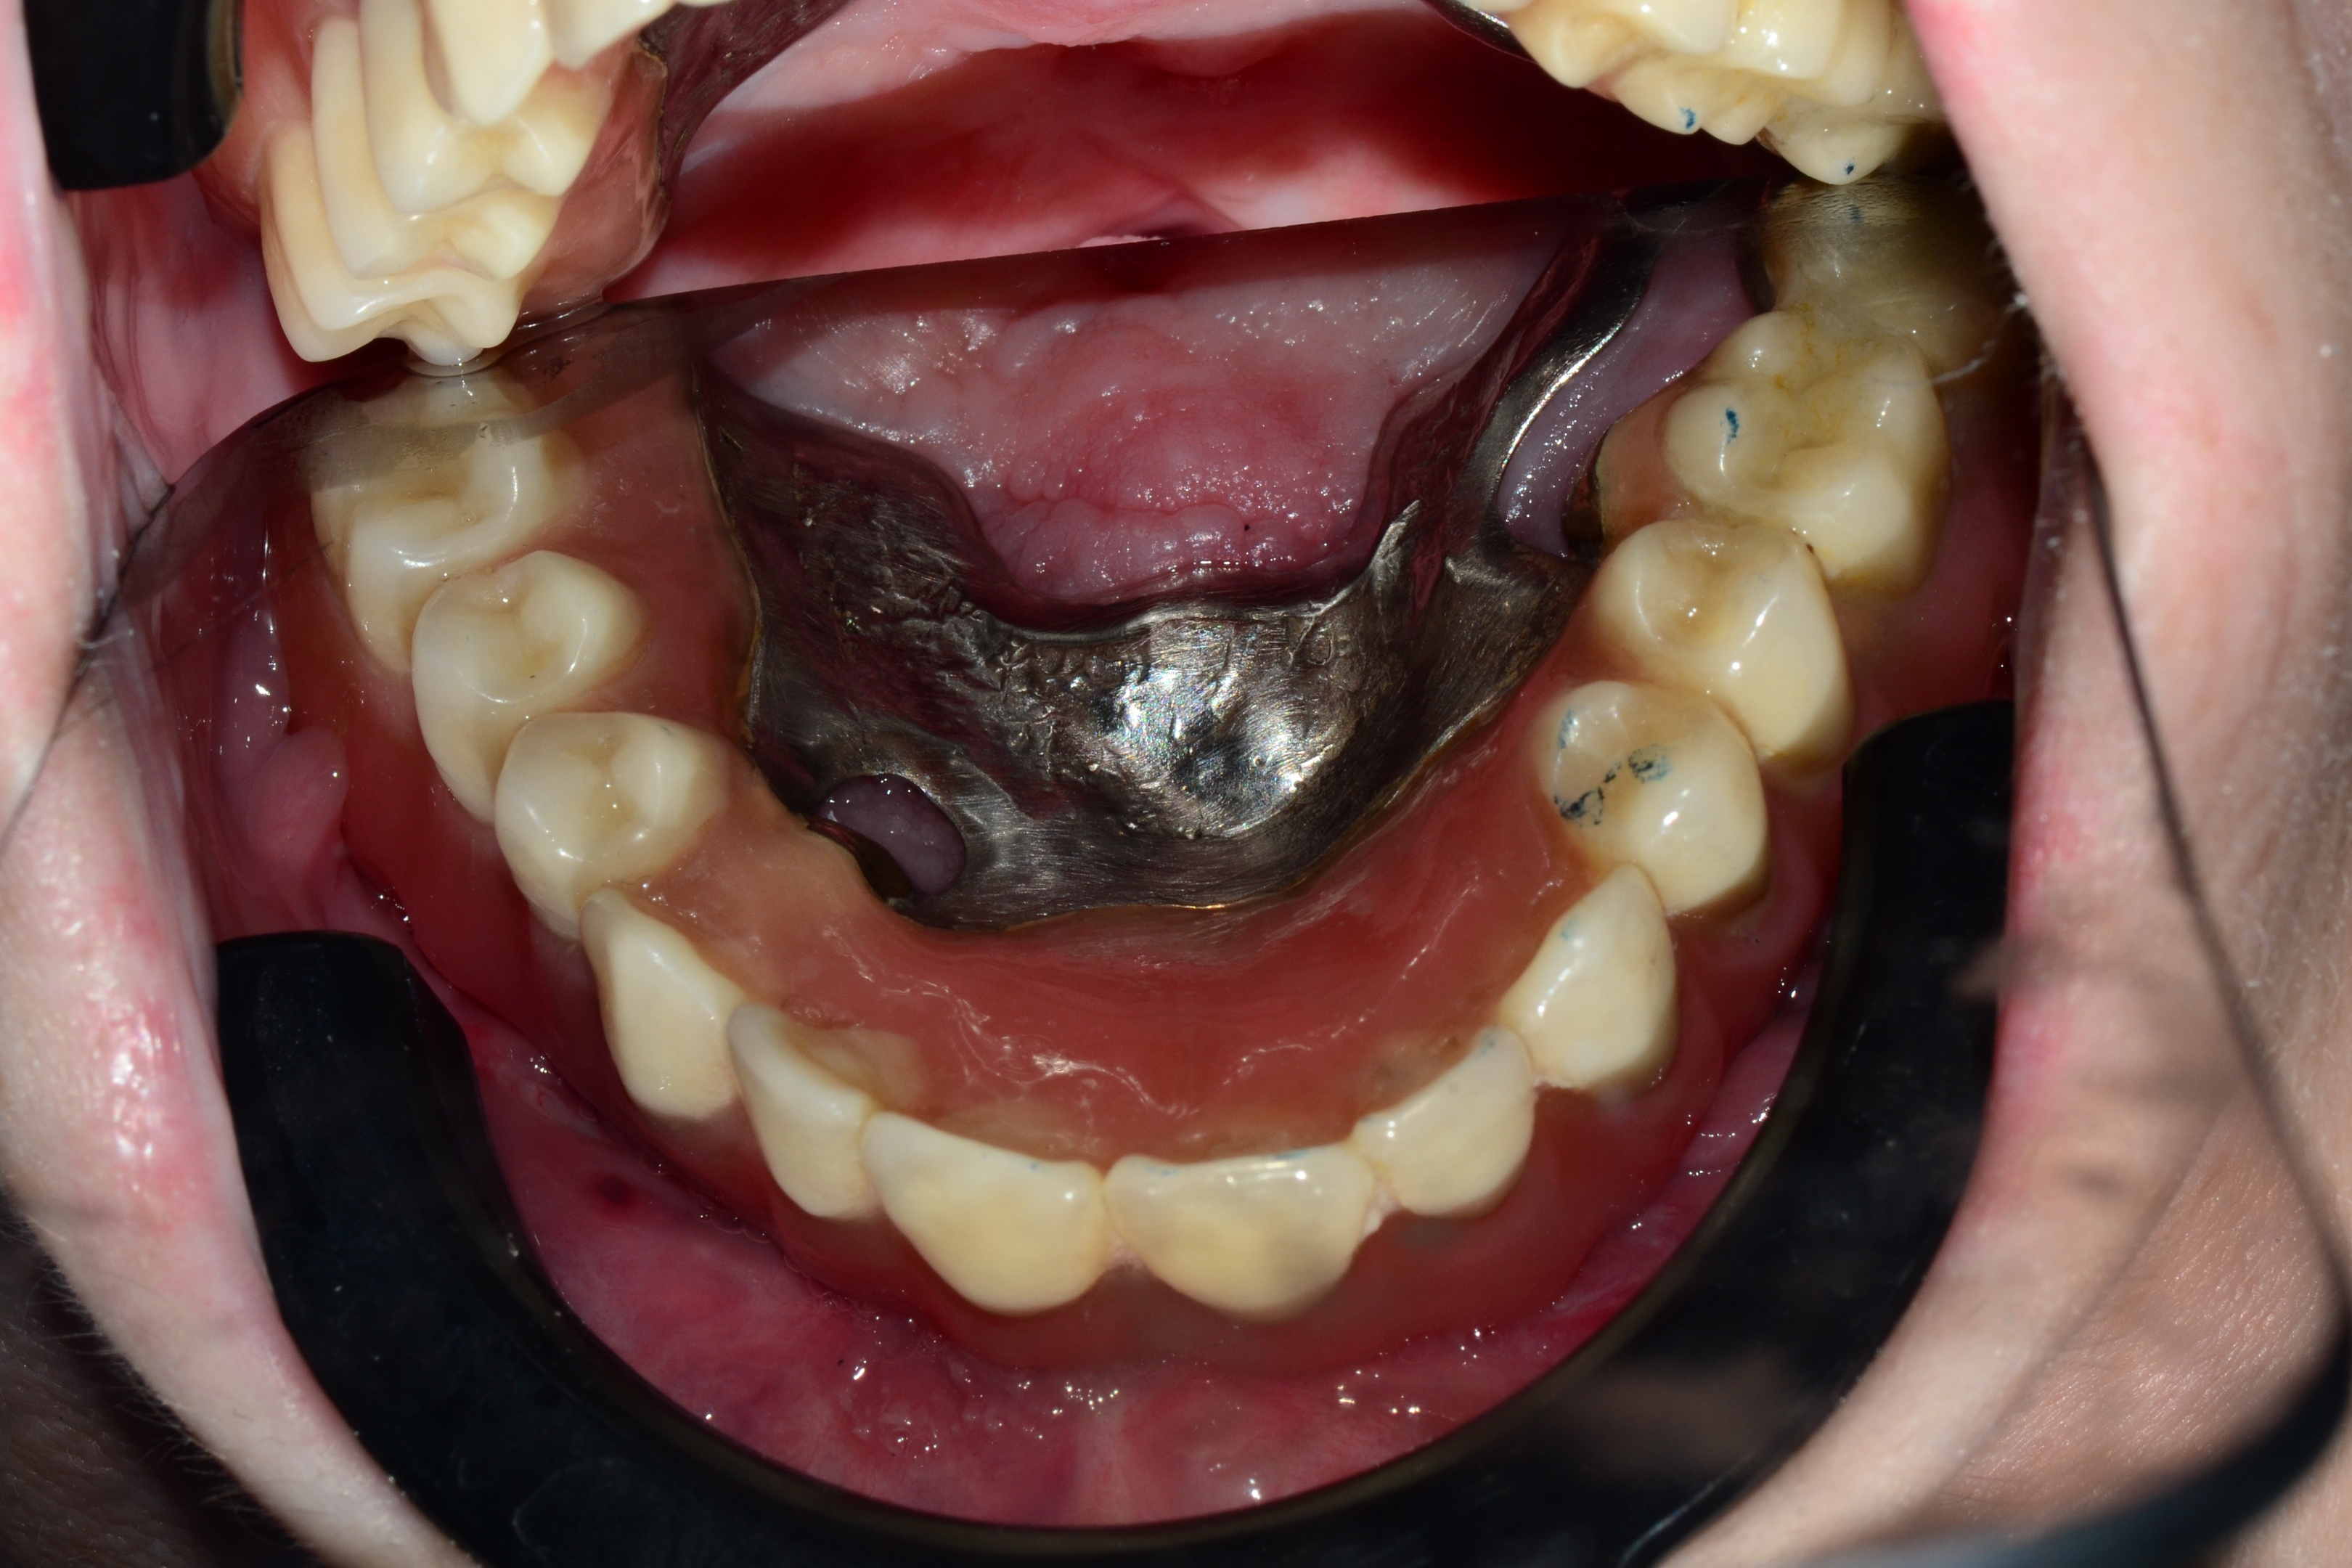

Izgled proteze u ustima

Ove krunice se sastoje od unutrašnje i spoljašnje krunice, koje prisno naležu jedna na drugu, čime stvaraju jaku silu trenja , i teško se odvajaju. Tada kažemo da imaju jaku silu retencije. Time se osigurava da proteza ostane na mestu, odnosno da ne ispada.

Najčešće se izrađuju od zlata, kako bi se osigurala njihova trajnost i što bolja retencija. Unutrašnja krunica se cementira na zub, a spoljašnja krunica se nalazi u protezi.